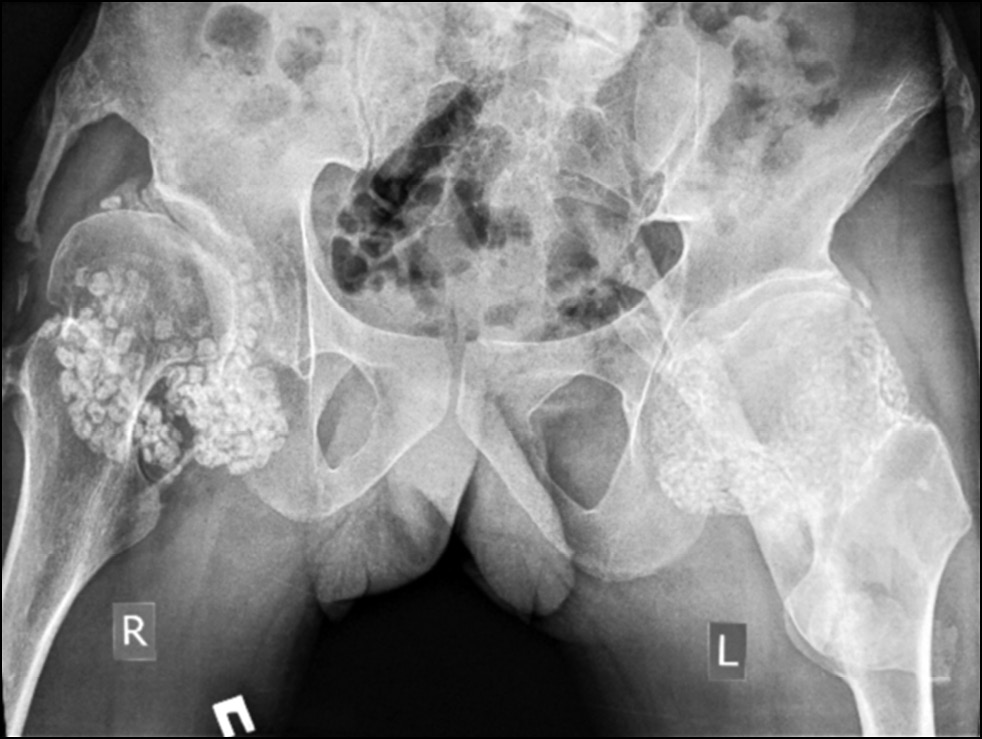

Control radiographs revealed multiple heterotopic ossifications of the axial and peripheral skeleton and submandibular region and multiplanar spinal deformity (Figs. 1–3). Computed tomography revealed synostosis of the 2nd–5th cervical vertebrae, which exhibited fusion of not only their posterior elements but also their bodies (Figs. 4 and 5). Synovial chondromatosis, one of the most common manifestations of FOP, was identified during a hip joint examination (Fig. 6). In addition to intra-articular chondromal bodies, heterotopic ossifications in the hip joints completely inhibit the movements in this skeletal region and significantly impeded walking (Figs. 7 and 8).

Fig. 6. Radiography of hip joints: marked synovial chondromatosis of both hip joints, heterotopic ossificates in the pelvis and hip joints.